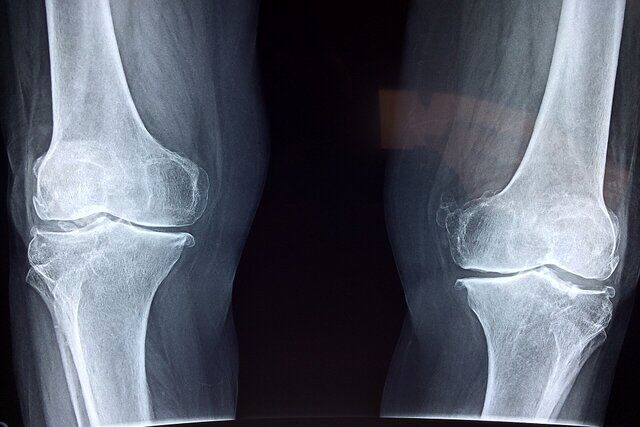

پوکی استخوان، یک بیماری شایع است که باعث کاهش تراکم و استحکام استخوان ها میشود و خطر شکستگی را افزایش میدهد؛ این…

آمار و ارقام بیانگر این است که یک زن از هر ۳ زن بالای ۶۰ سال و یک مرد از هر ۴ تا ۵ مرد بالای ۶۰ سال به پوکی استخوان…

پوکی استخوان بیماری است که معمولا تا اولین شکستگی ناشی از آن به وجود آید، علامت آشکاری ندارد، بنابراین یک بیماری خاموش…